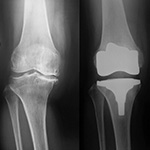

膝関節

Knee joint

変形性膝関節症や関節リウマチ・膝関節症の手術療法として人工膝関節全置換術(TKA)、単顆型人工膝関節置換術(UKA)、高位脛骨骨切り術(HTO)を施行しております。手術の目的は「痛みをとり、日常生活動作を向上させること」で、手術後は定期的に長期にわたり経過観察を行っています。変形性膝関節症や関節リウマチ・膝関節症の治療方法は患者様の年齢や背景に合わせて決めています。・・・